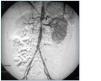

Pruebas complementarias: función renal y catecolaminas urinarias normales. Fondo de ojo: retinopatía hipertensiva grado I. Ecocardiografía: hipertrofia leve de ventrículo izquierdo. RNM craneal: glioma con afectación de quiasma y nervio óptico. Monitorización ambulatoria de presión arterial (MAPA): HTA diurna con presencia de dip nocturno. Ecografía-Doppler renal: flujo descendido en riñón derecho sugestivo de estenosis de arteria renal. Angio-resonancia abdominal: coartación severa de aorta abdominal con disminución de calibre del 85% y estenosis de arteria renal derecha, hallazgos que se corresponden con los obtenidos en la angiografía femoral percutánea (fig. 1).

Ante los hallazgos obtenidos, se decide la intervención quirúrgica de la paciente con realización de by-pass aorto-aórtico y reimplantación de la arteria renal derecha. La angiografía posterior demostró un patrón circulatorio restablecido (fig. 2). Precisó tratamiento farmacológico asociado con nifedipino oral durante cuatro meses. La función renal, cuatro años después de la intervención, está conservada y los flujos conservados en las ecografías doppler realizadas durante el seguimiento, con presión arterial normal.

Figura 1.